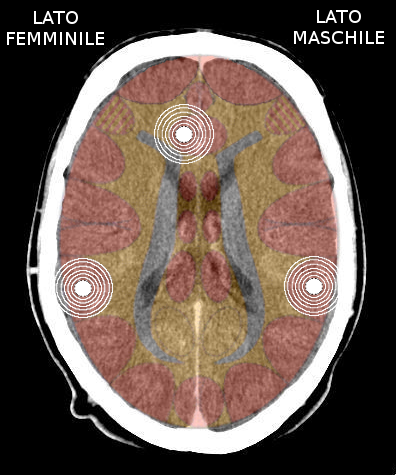

5.3.2 Chi può deprimersi?

- Un uomo destrimane con uno stato ormonale normale si deprime alla sua prima attivazione territoriale se l'impatto è molto forte, altrimenti diviene il cosiddetto "lupo beta", non è depresso ma remissivo.

- Una donna mancina con stato ormonale normale che vive un'attivazione "femminile" (spavento/paura, frustrazione sessuale, perdita di identità, non poter riconoscere il territorio).

Regola Biologica: una mancina attiva il lobo insulare destro, ma il suo percepito è sempre femminile. Impattando il lato maschile, diventa doppiamente femminile e potrebbe sviluppare una depressione. - Una donna destrimane dopo la menopausa o con livelli di estrogeni bassi. Ad esempio: in menopausa, in corso di assunzione di anticoncezionali ormonali, farmaci soppressori degli ormoni o chemioterapia. Il livello basso di estrogeni di una donna destrimane pone in chiusura il suo emisfero sinistro ad altre attivazioni. Diventa più mascolina e sperimenterà i vissuti in maniera più mascolina. Conseguentemente questi colpiranno l'emisfero cerebrale destro. Al seguito di queste attivazioni la donna diventa depressa (la cosidetta "donna esaurita").

Che predomini lo stato maniacale o lo stato depressivo è determinato da:

- Quale lato della corteccia abbia la massa attivatoria più grande (generalmente ed essendo più recente, il secondo SBS).

- Quale degli SBS si trovi attenuato.

La condizione maniaco-depressiva può cambiare costantemente da depressione o mania, o può rimanere permanentemente accebtuata in un lato.

Una persona può anche essere maniacale e depressa allo stesso tempo. In questo caso la depressione è "colorata" con mania o viceversa, dando come risultato una condizione mentale di tensione. Il grado del "disturbo" maniaco-depressivo o bipolare è determinato dall'intensità dei due (o più) SBS attivi.